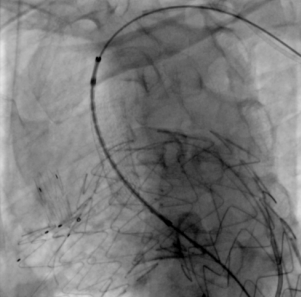

主体释放

经DSA造影确认位置准确,快速释放支架主体,助手牵拉并释放分支支架,再行造影后确认,支架定位准确。

治疗车怎么推【弓部重建直通车】梅州市人民医院心内科团队运用Castor®分支型支架联合预开窗技术治疗主动脉弓动脉瘤合并迷走右锁骨下动_https://www.jmylbn.com_新闻资讯_第11张

释放支架